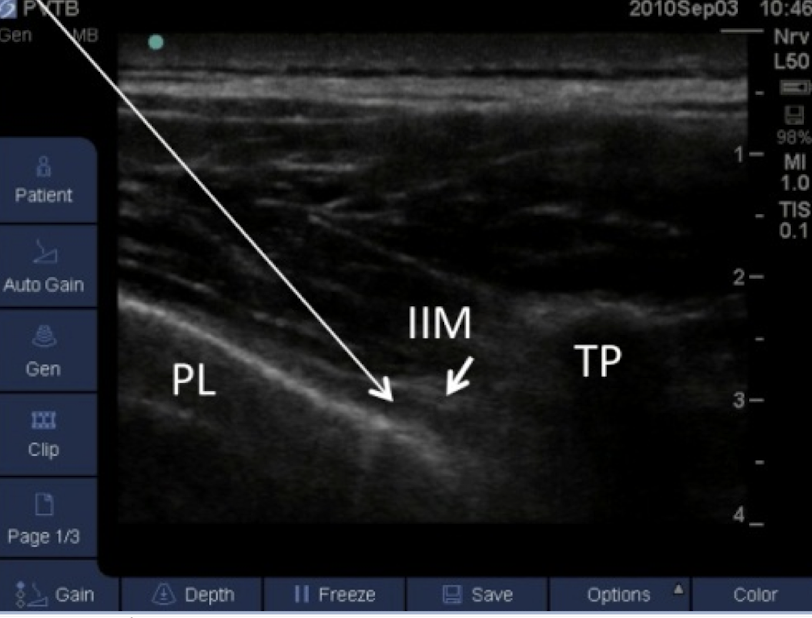

9

Q

Name the block and structures

A

transverse in plane PVB

pleural line

internal intercostal muscle

transverse process

How well did you know this?